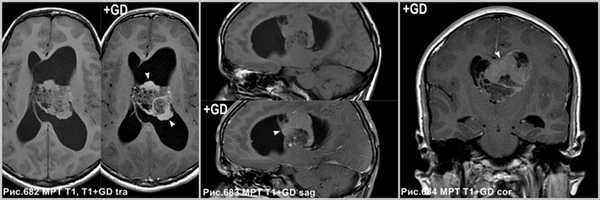

Центральная нейроцитома в виде неоднородной структуры объёмного образования, расположенного в боковом желудочке, связанное с прозрачной перегородкой (звёздочки на рис.679-681), сопровождающееся расширением бокового желудочка (головки стрелок на рис.680, 681). МРТ демонстрирует врастание опухоли в стенку бокового желудочка левого полушария большого мозга (стрелки на рис.680, 681).

![central_neurocytoma_3]()

На МРТ в режиме Т1 после контрастного усиления определяется неоднородное накопление контраста в солидных участках опухоли (головки стрелок на рис.682-684). В области внутриопухолевых кист усиление отсутствует.